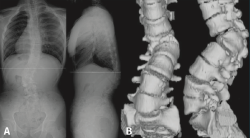

Figura 5. Espondiloartropatía degenerativa.

Otros hallazgos radiológicos frecuentes, como las anomalías congénitas de transición lumbosacra, espondilolistesis, secuelas de epifisitis, la espina bífida oculta, las escoliosis leves o moderadas, la hiperlordosis, espondiloartropatía, etc., se encuentran casi por igual en pacientes con y sin dolor lumbar (Figuras 5, 6 y 7)(22,23).

Figura 6. Secuelas de epifisitis. Reproducido de Perolat et al.(22).

Figura 7. Hiperlordosis. Reproducido de Oakley et al.(23).

Figura 10. Escoliosis secundaria a hemivértebra.

Constituye una técnica muy útil para evaluar las anomalías anatómicas de la columna vertebral (Figura 10).

Figura 11. Malformación vertebral en resonancia y tomografía axial computarizada.

La TAC visualiza con bastante precisión el tejido óseo, siendo claramente superior a la RM para ello. También permite visualizar los tejidos blandos intra- y paraespinales, aunque la RM es muy superior en la evaluación de estos tejidos, por lo que está siendo desplazada por esta para el estudio de los problemas discales, degenerativos y radiculomedulares (Figura 11).